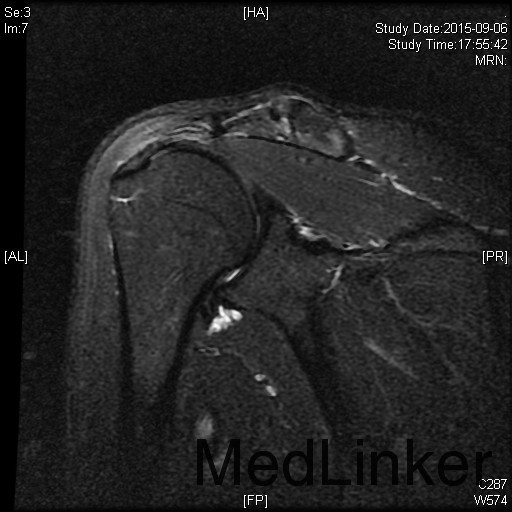

主诉:左肩扭伤后疼痛不适伴弹响10余年,加重3月。 现病史:患者10余年前扭伤左肩关节后出现疼痛不适等症状,伴活动时弹响,以运动时明显。患者当时未重视,未就诊。10余年来患者左肩疼痛不适症状反复发作,曾至外院行局部理疗、小针刀等保守治疗,效果不佳。3月前患者再次扭伤左肩,当即感觉左肩症状加重。来我院就诊,我院行MRI检查示:左肩盂唇信号异常及肱二头肌长头肌腱信号异常。

1、诊断:左肩创伤性前不稳定,左肩SLAP损伤。 2、治疗:全麻下行左肩关节镜下前盂唇、上盂唇修补术。